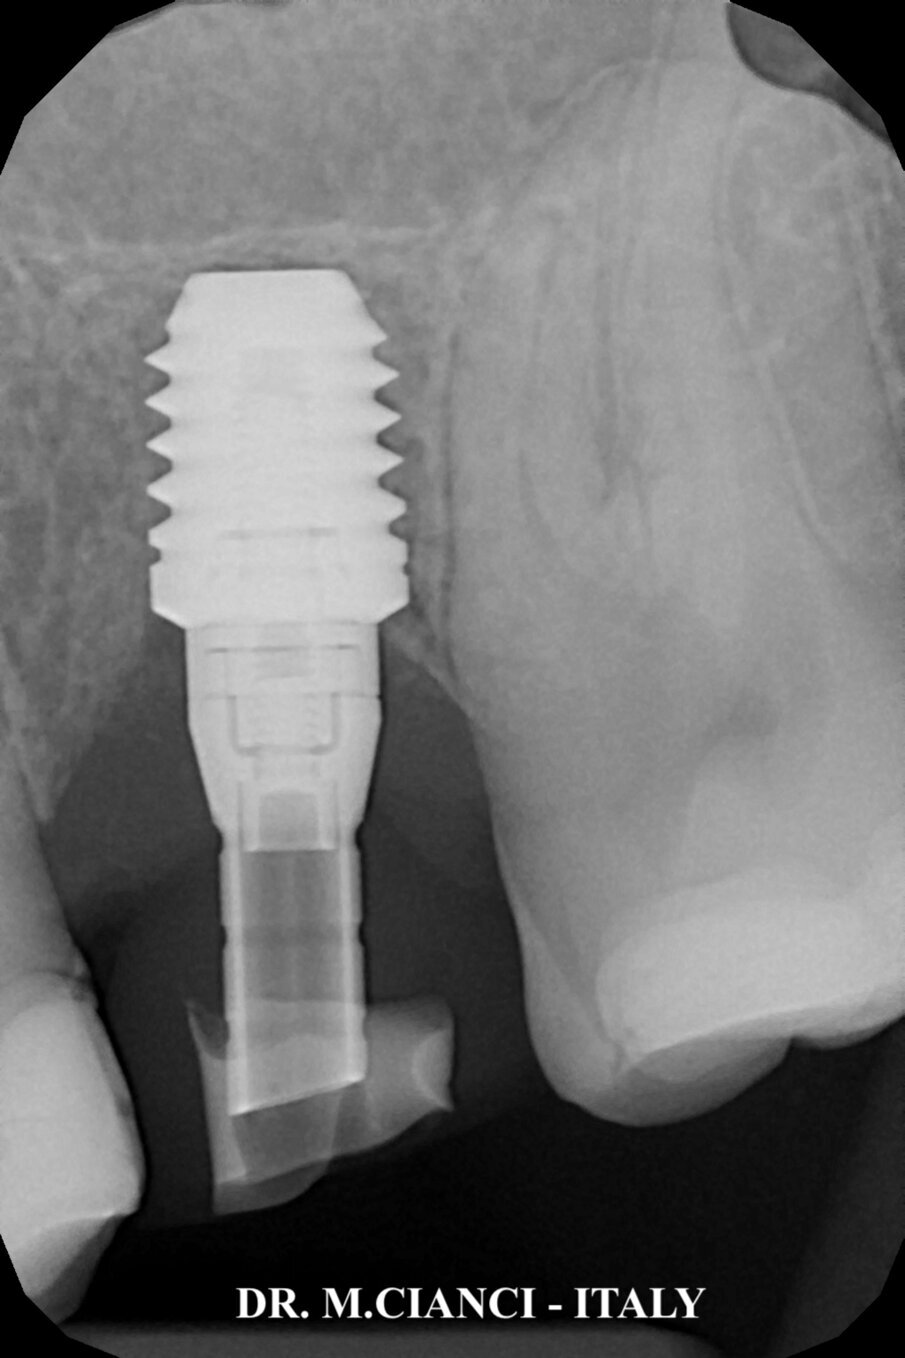

Sollevato un lembo a spessore totale vestibolo-palatale sono state utilizzate frese di diametro progressivo sottopreparando il tragitto implantare al fine di ottenere una stabilità primaria necessaria ad eseguire il carico immediato: ultima fresa di diametro 4,8 mm utilizzata solo fino a 4 mm di profondità sottopreparando l’apice del tunnel osseo prima di inserire l’impianto. Gli ultimi 0,5 mm sono stati fresati con una speciale fresa a taglio frontale di diametro 4,5 mm che ci ha permesso di sollevare la membrana di Schneider mantenendola integra (Fig. 6). A questo punto, una volta verificata la negatività della manovra di Valsalva, è stata inserita sul fondo della preparazione una membrana di fibrina autologa elaborata con la frazione 1 del PRGF Endoret® , meno ricca di fattori di crescita piastrinici, a protezione della membrana sinusale e con un condensatore abbiamo eseguito una lieve pressione al fine di scollare la membrana a questo livello: il Sinus Lift è stato completato inserendo una piccola quantità di biomateriale autologo mischiato con la frazione 2 di PRGF più ricca di fattori di crescita13. L’impianto corto 5.5 x 7,5 mm è stato avvitato infine con un torque di 40 NCM e lasciato volontariamente esposto extra-cresta per 1 mm in sede vestibolare e 2 mm in quella palatale (Fig. 7). Abbiamo poi completato la rigenerazione vestibolo-palatale utilizzando sempre l’osso autologo del paziente mischiato alla frazione 2 di PRGF e coperto gli innesti con uno primo strato più profondo di coagulo frazione 2 ed un secondo strato più esterno di membrana di fibrina frazione 1 (Figg. 8, 9).

Conclusa la rigenerazione è stato avvitato direttamente sull’impianto un abutment Transepiteliale Unit di 1,5 mm (torque di 30 NCM) la cui finalità è quella di garantire una chiusura completamente ermetica e biologica tra impianto e elemento protesico prima provvisorio e poi definitivo (Bioblock® Concept sviluppato da BTI Biotechnology Institute) (Fig. 10). Presa l’impronta con un cucchiaio individuale aperto, tre ore dopo la chirurgia abbiamo consegnato la capsula provvisoria in composito avvitata con un torque di 20 NCM procedendo subito con la funzionalizzazione dell’impianto corto (Fig. 11).